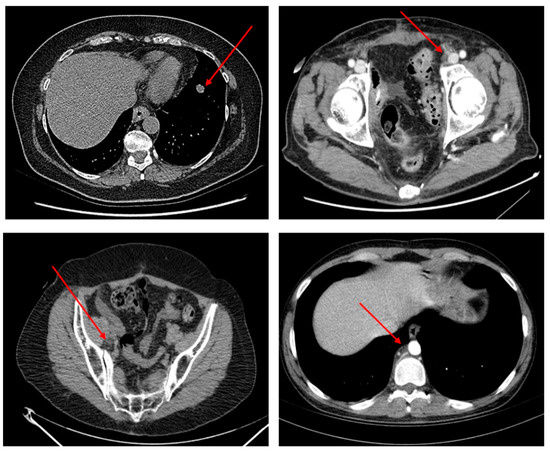

Therefore, in light of the RECIST criteria, the oncologist manually identifies the TARGET lesions and these serve to monitor the oncological disease over time and therefore, in this case, the effectiveness of the immunotherapy treatment. In terms of interest in this work, only one TARGET lesion was identified, the most significant according to the RECIST criteria adopted above to monitor the disease during immunotherapy treatment. Figure 4 shows some examples of TARGET lesions manually identified by oncologists who have been used by bladder cancer patients and inserted into the dataset used to train and validate the proposed pipeline.

Figure 4.

Some instances of TARGET lesions (identified by red arrows) manually selected by oncologists for tracking the immunotherapy treatment response.

Figure 4 shows some TARGET lesions (metastasis of the primitive bladder tumor in the thoracic and pelvic-abdominal area) selected by the oncologist according to the RECIST criteria mentioned above and which is therefore used for clinical evaluations of the anti-PD-L1 immunotherapy treatment.